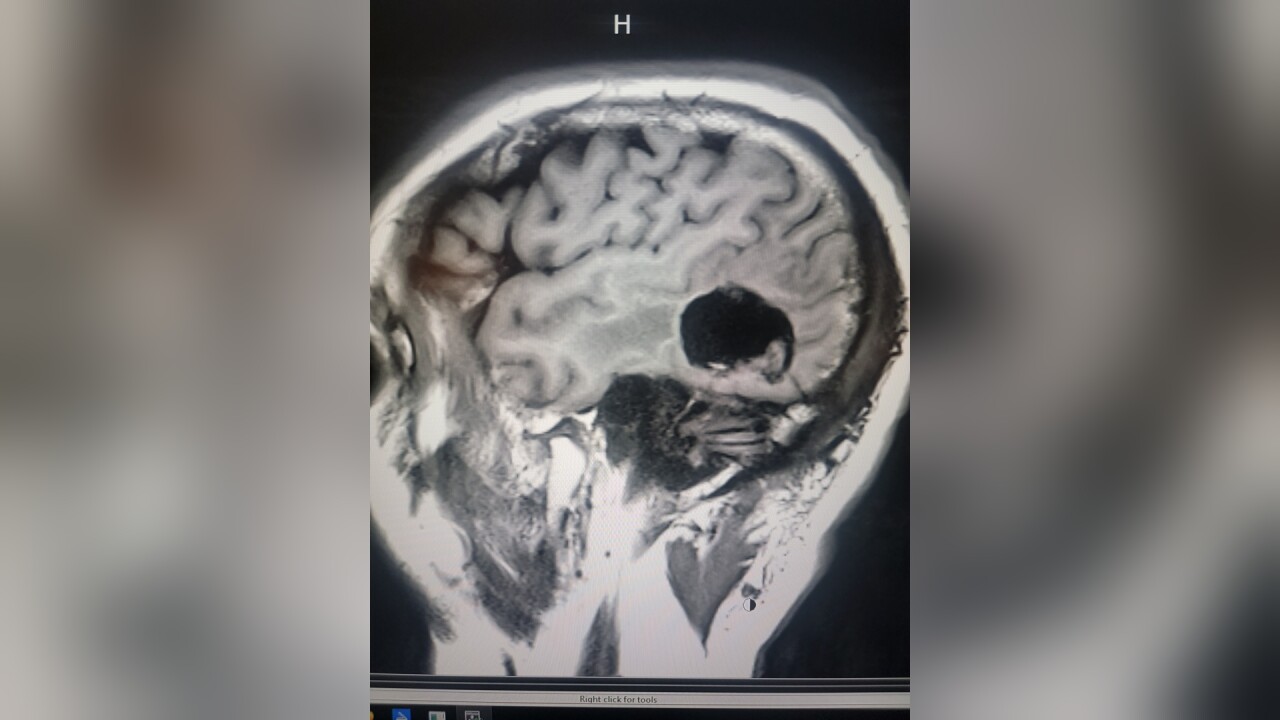

The fire truck pulled over, and Sean basically blacked out. By the time he got to the hospital and had an MRI taken, the diagnosis was clear: Sean had a large glioblastoma - a tumor -on the back left part of his brain. Two days later, he was in surgery.

When Sean did wake up, it was to good news. Billings Clinic Neurosurgeon Dr. Vance Fredrickson was able to remove almost the entire tumor.

"The goal is always to get as much as you can safely - there's a longer survival if you get more," Fredrickson said. "But there's also a shorter survival if you cause major deficits trying to get the tumor out."

Deficits meaning basic motor functions - speech, sight, etc. For the next year, Sean looked and felt great, and the Laurel community rallied behind him, holding a number of fundraisers to help with his recovery. But then the tumor started to grow back, and Fredrickson needed to go back in.

"He said, 'I want to go a little deeper if that's ok, but you’re probably going to lose some of your vision,'" Sean remembers of the conversation. "I said I’m totally fine with that - just get that out of my head."

Once again, the outcome was extremely positive: Sean's most recent scans showed the tumor shrinking, and he has nothing but praise for all of the medical personnel involved. But life is much different now.